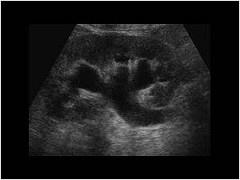

问题 以下哪种声像图,最易诊断为肾积水 ?(?)

选项 A.肾皮质变薄 B.肾盂、肾盏、集合系统充满无回声 C.肾盂、肾盏、集合系统回声增强 D.肾形态失常 E.肾实质多发无回声

答案 B